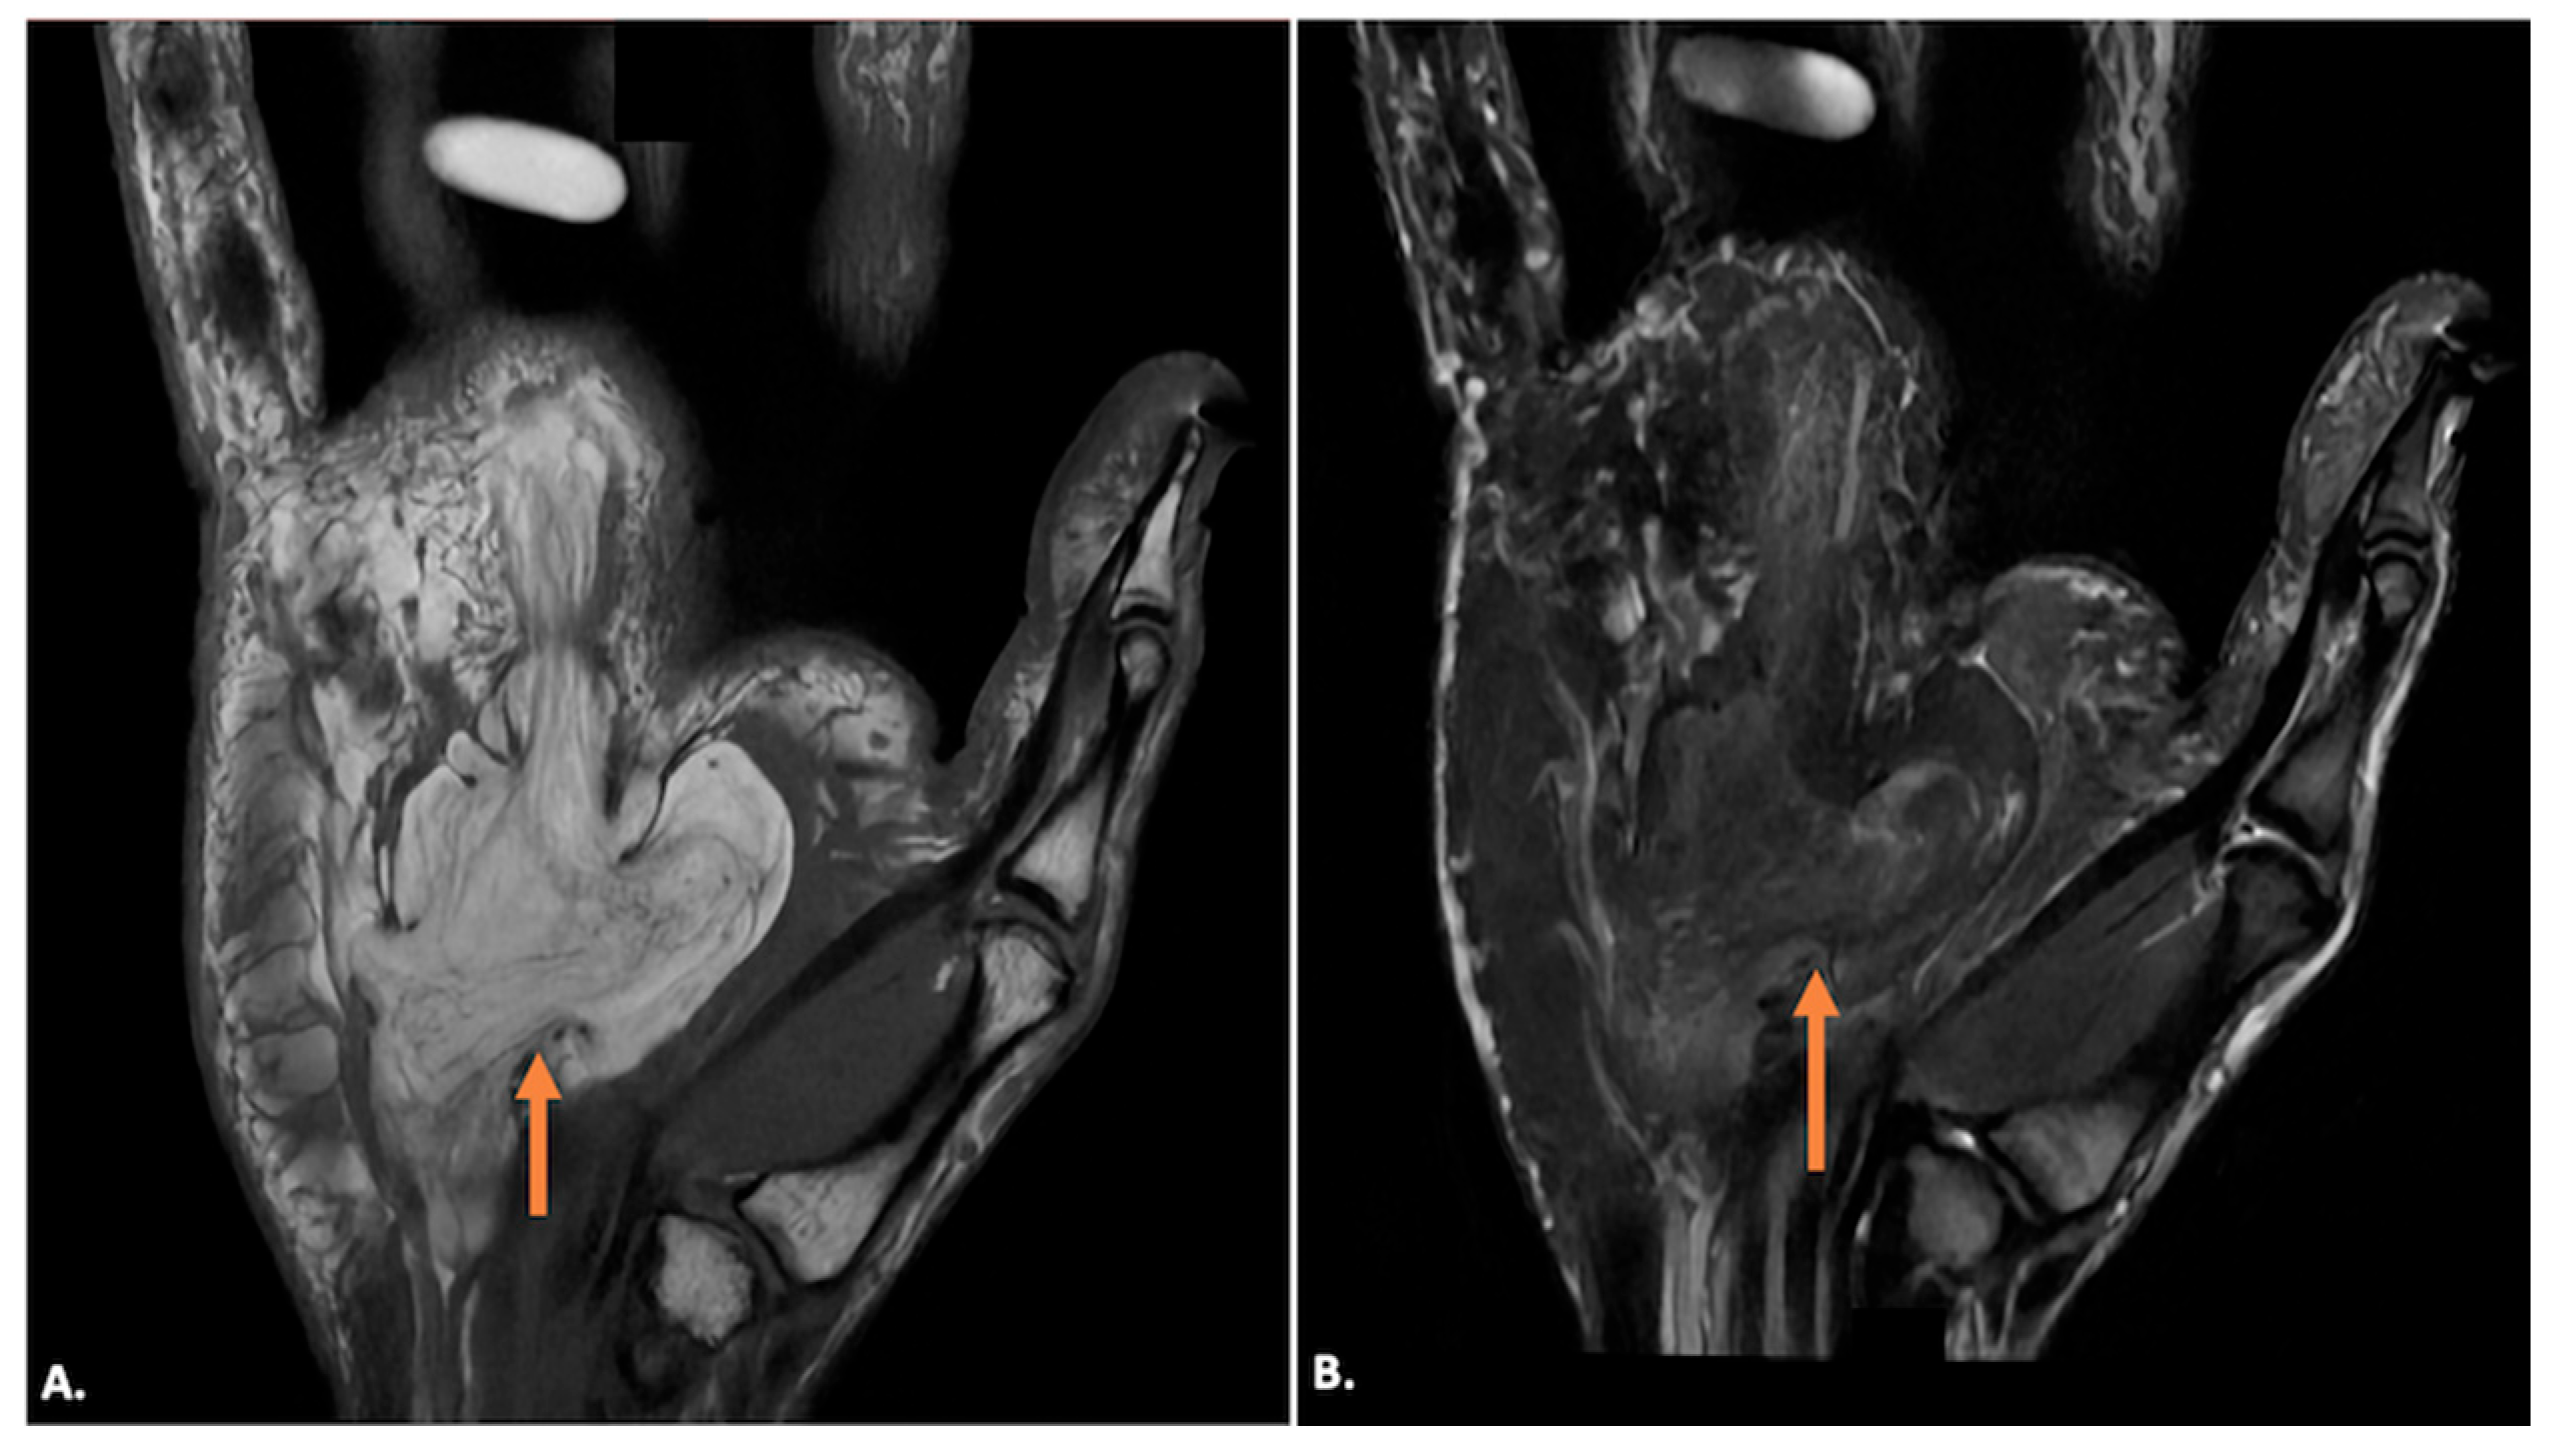

4.4. Neoplastic Conditions

| Lipoma | Well-defined, iso-to-hypoechoic mass, possibly with echogenic striations. No internal vascularity on Doppler. | Hyperintense on T1- and T2-weighted images. Homogeneous fat suppression. No post-contrast enhancement. Septa or nodules may indicate atypical lipomatous lesion. |

| Hemangioma | Hypoechoic or heterogeneous mass with anechoic areas (vascular channels). Doppler shows significant internal vascularity with low-resistance arterial and venous flow. | Hyperintense on T2, low signal on T1. Heterogeneous intense enhancement post-contrast. |

| Neurogenic Tumours (Schwannoma/Neurofibroma) | Well-defined, hypoechoic mass, sometimes with a “target” appearance (hypoechoic centre, hyperechoic rim). Minimal vascularity on Doppler. Follows ulnar nerve course. | Iso- to hypointense on T1, hyperintense on T2. May show “target” appearance. Heterogeneous enhancement. Follows ulnar nerve course. |